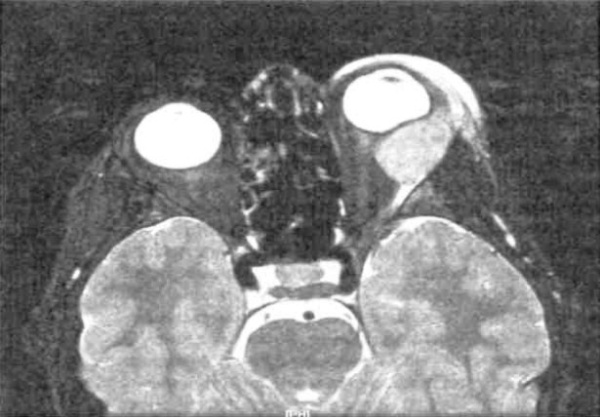

Африканская лимфома Беркитта. Массивное поражение обеих глазниц и вторичная кератопатия и изъязвление роговицы вследствие ее обнажения у ребенка-африканца. Неафриканская лимфома Беркитта. Отек век и экзофтальм справа у ребенка 26 месяцев. Аксиальная Т2-взвешенная МР-томограмма: пациент, представленный на рисунке выше; вдоль наружной стенки глазницы определяется удлиненное объемное образование. Гистологический препарат новообразования, показанного на рисунке выше: определяются пласты лимфоцитов с островками гистиоцитов (гематоксилин-эозин, х300). СПИД-ассоциированная лимфома Беркитта. Остро развившиеся отек века и экзофтальм у подростка. КТ, аксиальная проекция: пациент, представленный на рисунке выше; определяется диффузное поражение переднего отдела глазницы опухолью. Отмечен выраженный эффект химиотерапии.

При КТ и МРТ определяется объемное образование верхней челюсти, вторично прорастающее в глазницу. При американской форме опухоли на томограммах обычно выявляются объемное образование придаточных пазух носа и вторичное прорастание опухоли в глазницу.